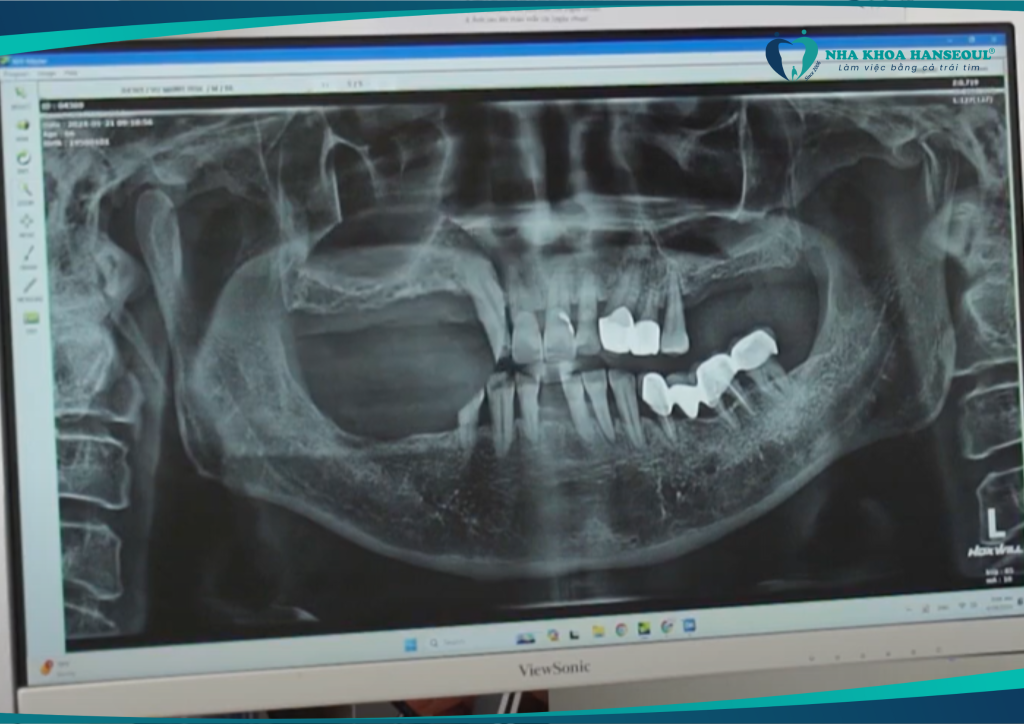

Sau khi được các bác sĩ thăm khám và chụp phim kỹ lưỡng, chú được chỉ định phục hình toàn diện bằng công nghệ cấy ghép răng Implant Hansafe. Đây là giải pháp hiện đại giúp phục hồi răng mất an toàn, không đau, ăn nhai như răng thật.